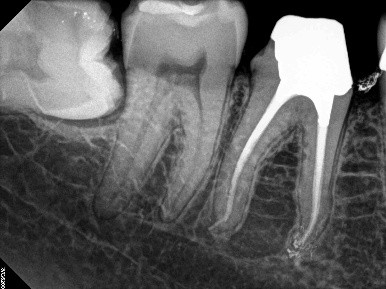

17. (Select ONE or MORE correct answer)

Regarding tooth 4.6, there is evidence of